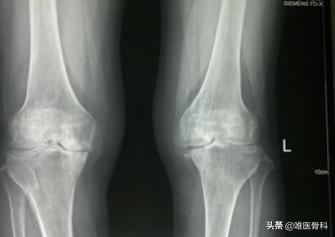

我们在门诊观察严重膝关节骨关节炎患者的X光片时常常发现,骨关节炎患者往往会有骨质增生(长骨刺)的表现,因此骨关节炎患者也会存在骨质增生的情况,但这并不意味着骨质增生就是骨关节炎,或者说骨质增生导致了骨关节炎的发生。事实上仅有骨刺而无其他症状(比如关节疼痛、肿胀及关节活动受限等)的患者不能构成骨关节炎。

骨质增生常常是骨关节炎的表现之一